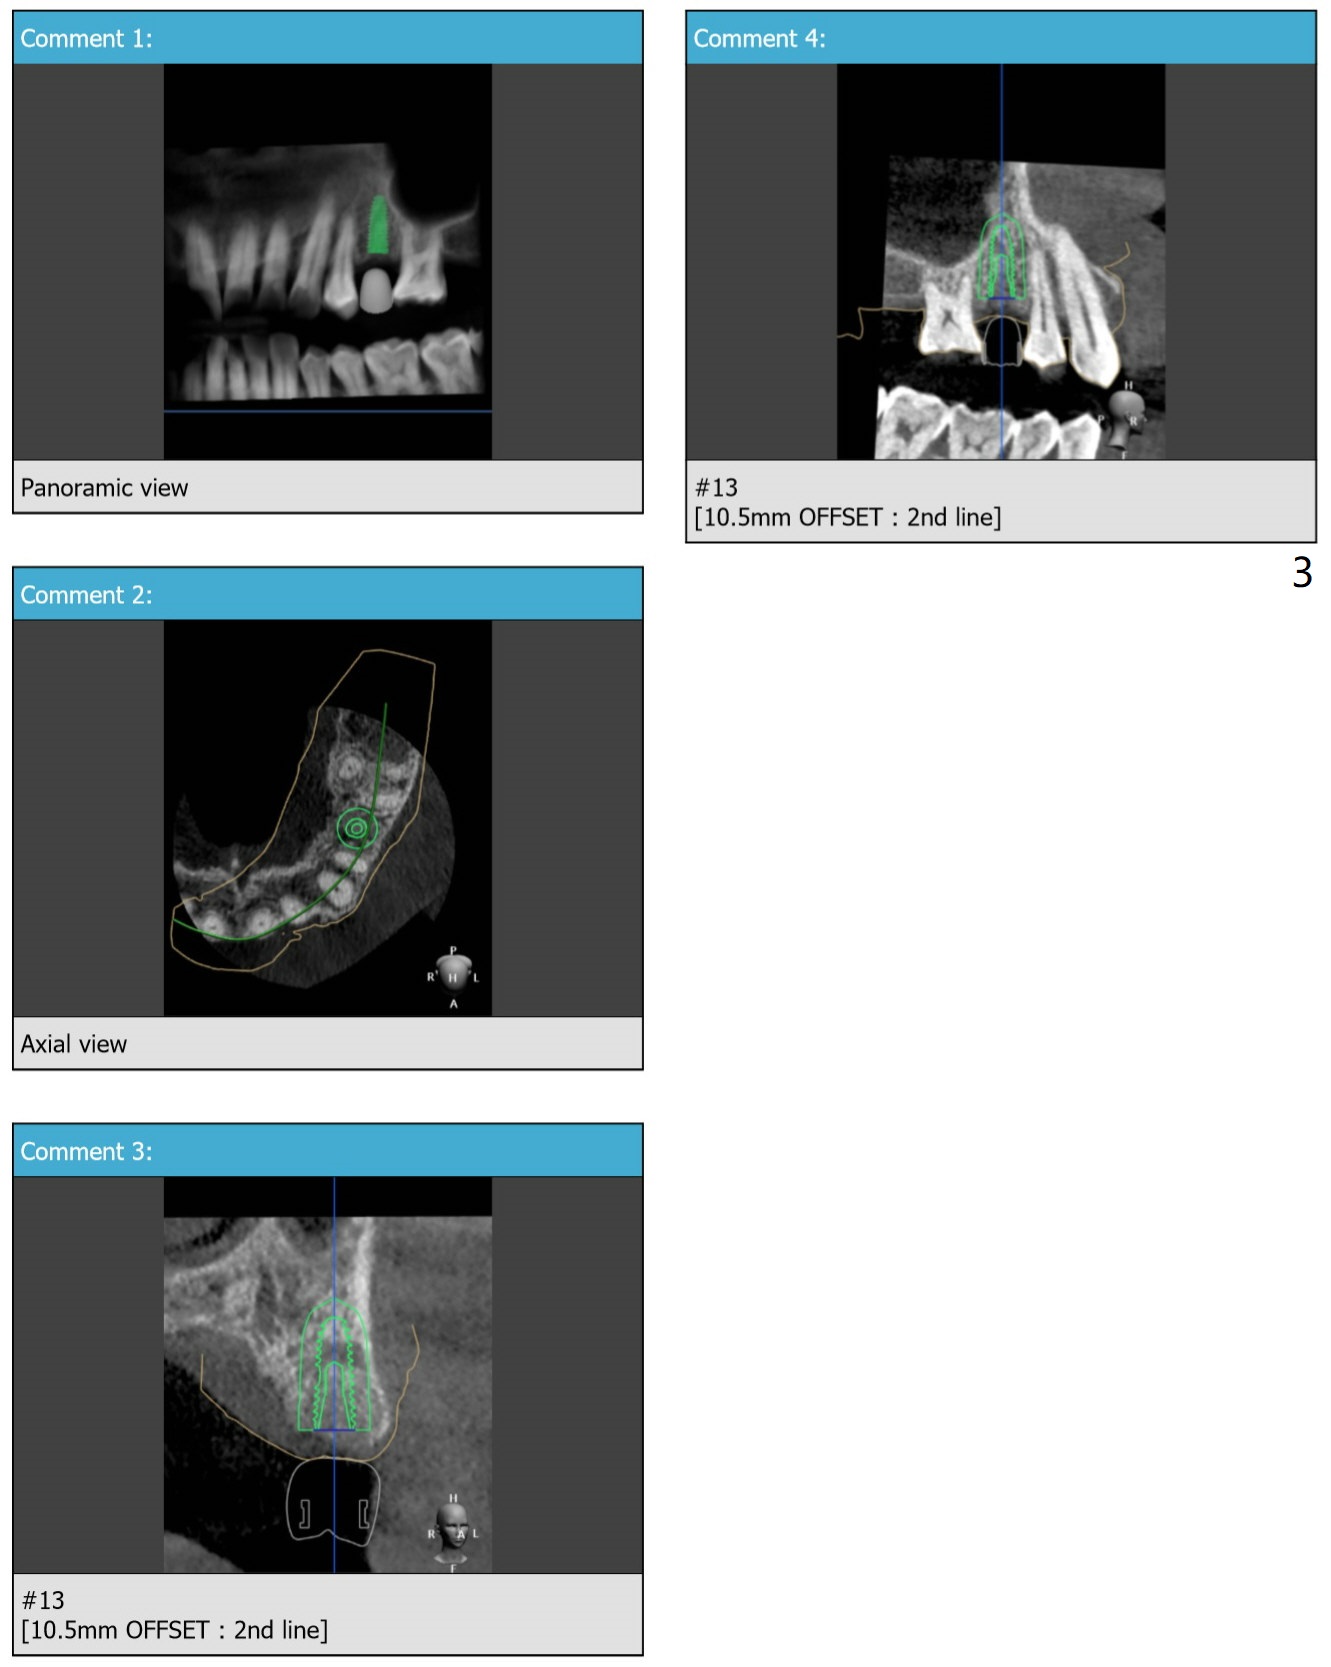

~ 6 months post socket preservation, bone density ~ 1000 units.

Xin Wei, DDS, PhD, MS 1st edition 03/02/2020, last revision 03/10/2020